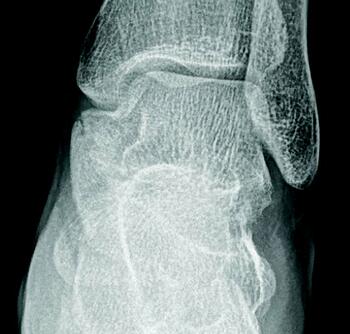

A tarsal coalition exists when there is a congenital, complete or incomplete union between two or more tarsal bones causing restricted motion or absence of motion. Tarsal coalitions remain challenging for the foot and ankle physician and surgeon. Their clinical hallmarks are primarily pain, rigid pes valgus and/or rigid pes planus deformity, and often tonic peroneal muscle spasm. Although the diagnosis of a tarsal coalition is often readily apparent upon clinical examination, diagnostic imaging is confirmatory and often aids in planning any necessary surgical intervention. Sequentially, the author always obtains radiographs of the involved foot first followed as necessary by advanced imaging with either computerized tomography (CT) or magnetic resonance imaging (MRI) scans, or in some instances of incomplete tarsal coalition, both CT and MRI.1

Recently, the literature presents arguments for the inclusion of the size and type of talocalcaneal coalition, and the degree of heel valgus as factors to consider when deciding between joint resection and joint fusion.3-11 Some hypothesize that the size of a talocalcaneal coalition inversely correlates with the success rate of resection, and some researchers used preoperative advanced imaging studies, particularly CT, to investigate.3,4 Arbitrarily, based only on their personal experience, these investigators concluded that talocalcaneal coalitions involving greater than 50 percent of the talocalcaneal joint are less amenable to surgical resection.3,4 More recently though, several authors challenged this subjective assumption and instead determined that no definitive talocalcaneal coalition size precludes an attempt at resection in every patient.5-7